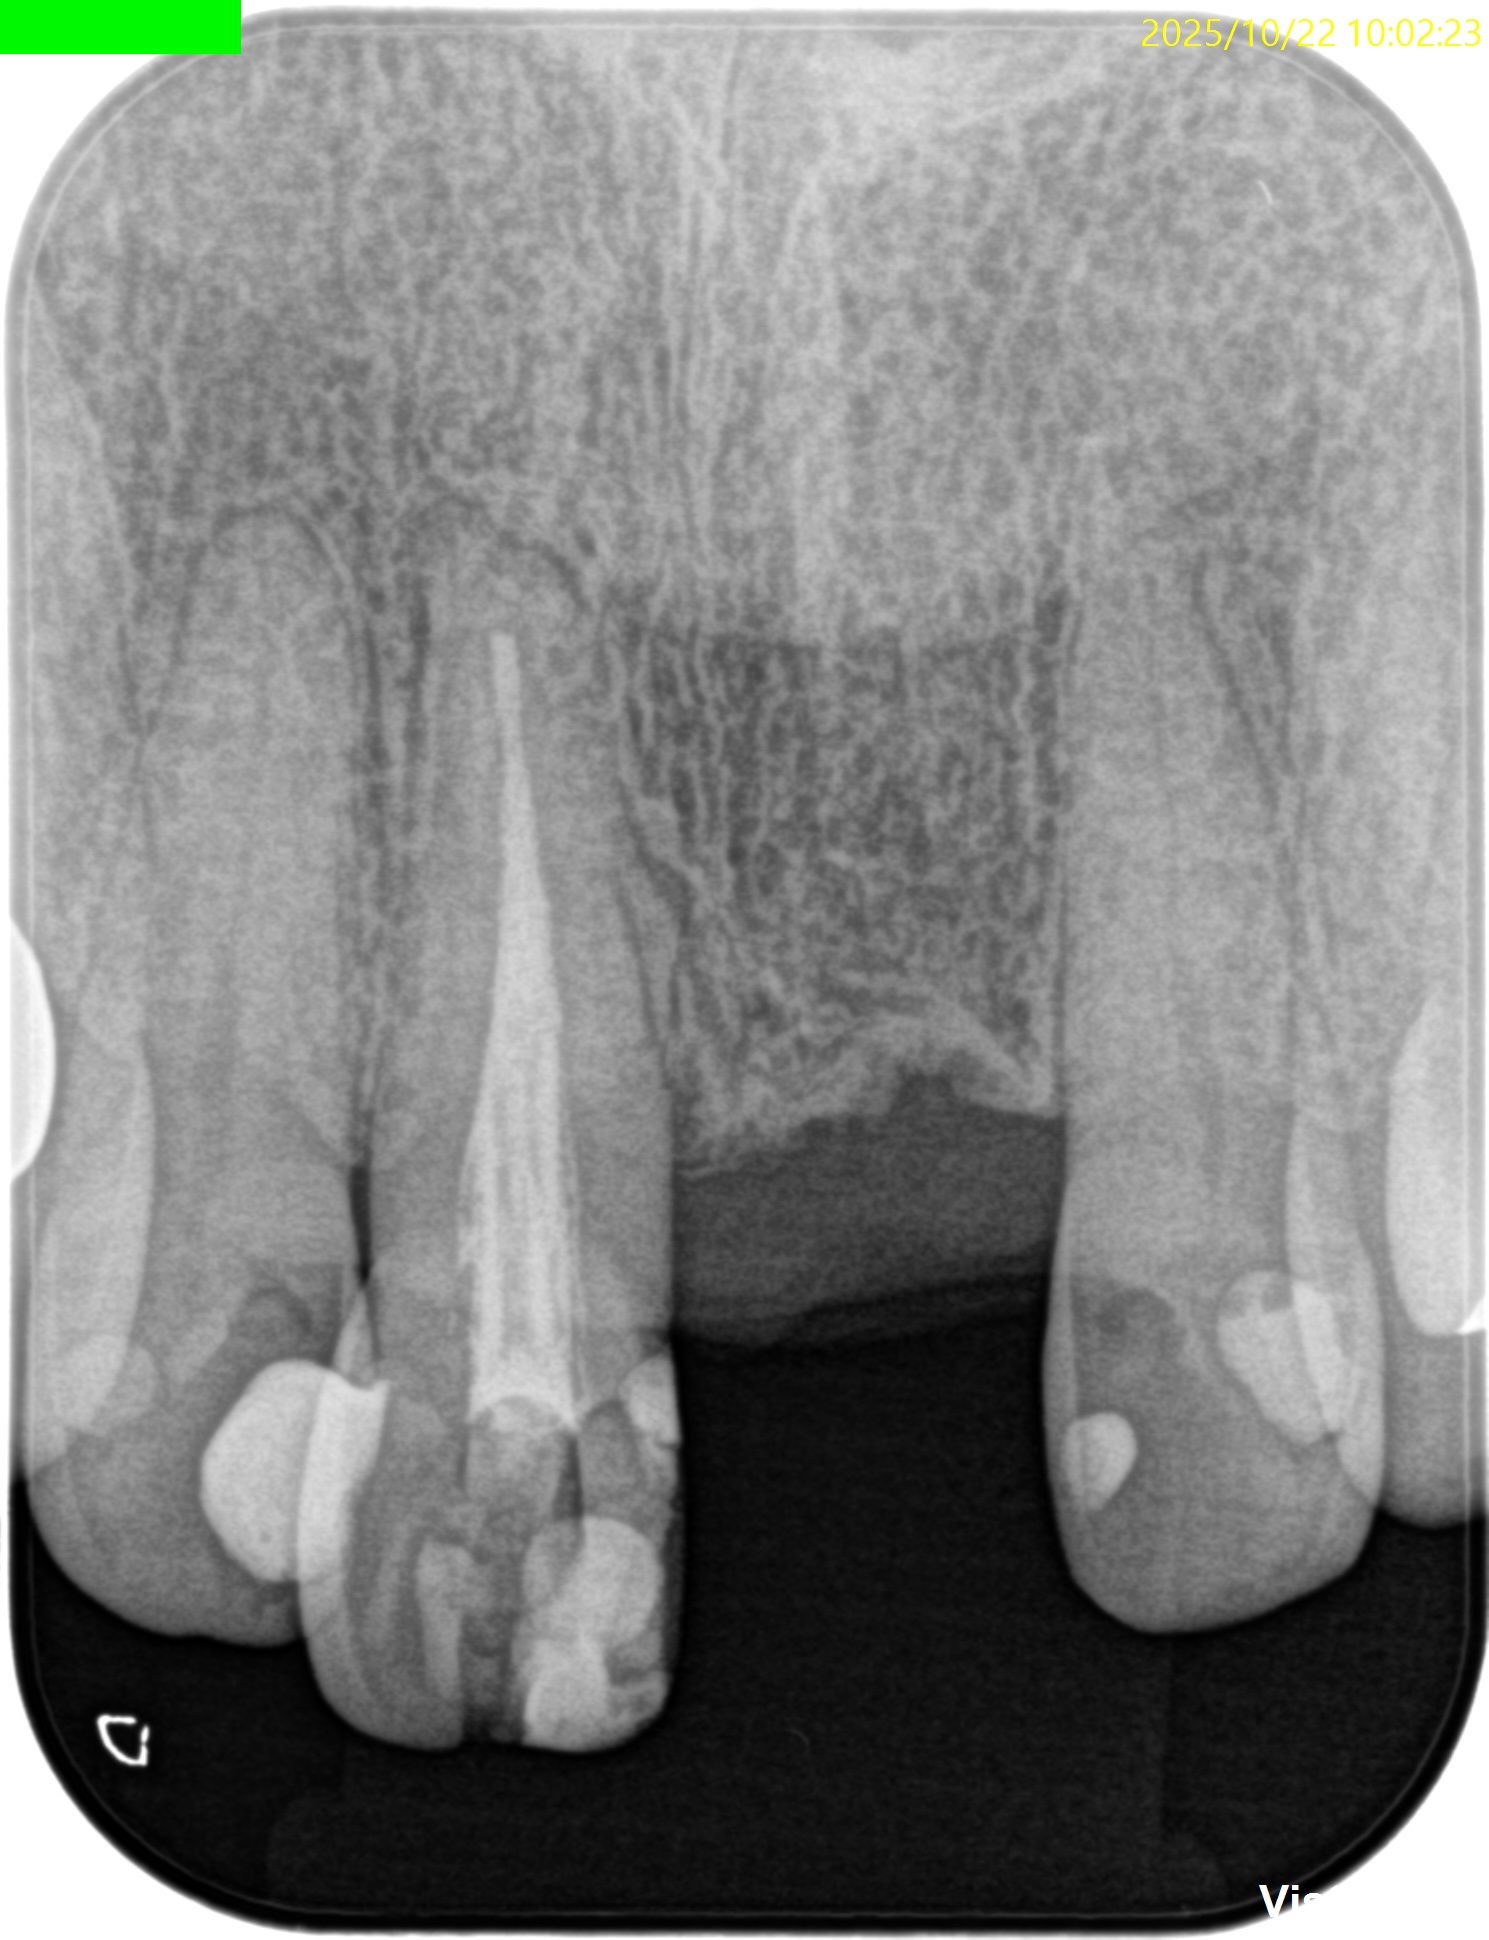

歯内療法学的検査(2025.10.22)

PA(2025.10.22)

CBCT(2025.10.22)

歯内療法学的診断(2025.10.22)

Pulp Dx: Previously treated

Periapical Dx: Symptomatic apical periodontitis

Recommended Tx: Re-RCT+Core build up with Fiber Post